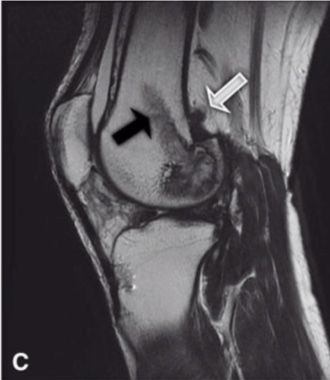

因此,對於這樣的疾病,國際上大多採用複合的方式來作為治療。在過去的方法,醫師先進行第一次手術,將膝蓋前方的腫瘤清除。之後使用石膏固定兩週後,再行第二次手術將膝蓋後方的腫瘤清除。接著在手術六週後,加以局部的低劑量放射線治療,以減少腫瘤復發的機會。

而我們台北榮總骨骼肌肉腫瘤治療暨研究中心將這個傳統的方式進行修正,將第一、第二次手術合併在一起,手術後不用石膏固定,反而在手術後隔天開始積極的復健運動。根據我們的研究結果,這個方法可以使病患得到更好的手術後功能恢復。我們團隊的這個成果,在2012年發表於知名的骨科醫學期刊 Clinical Orthopaedics and Related Research(CORR)中(*),目前已經成為全球治療彌漫型的腱鞘巨細胞瘤的標準做法。

(5) 膝蓋後方之腫瘤,常與神經血管發生沾黏 (5) 再將關節腔外的腫瘤,儘可能的切除 (7) 打開後側關節腔,移除關節內的腫瘤 (8) 可能殘餘部分之腫瘤於關節腔中與神經血管壁上